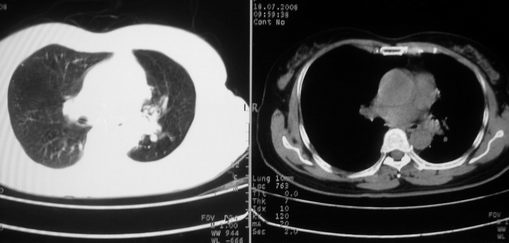

以下是引用李衡钧在2008-7-24 14:24:00的发言:[br]左侧胸廓变小,左肺上叶见大面积致密阴影,其内有空洞及不规则钙化。上纵隔略向左移位,上肺胸膜增厚。左肺门及纵隔淋巴结增大。右肺见散在的致密结节影。[br]印象:继发性肺结核。